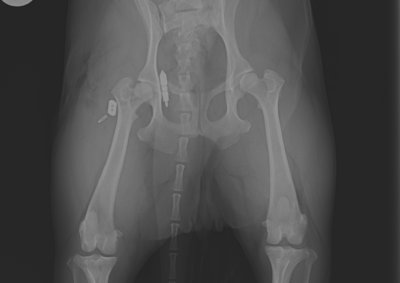

注意 ボタンをクリックした先に、治療中および手術中の画像が説明で使用されている場合がございます。 そのような画像に弱い方は閲覧なさらないようお願いいたします。 整形外科 若齢犬の橈骨固定術 #271 整形外科 前十字靭帯断裂(中型犬)に対するCBLO #255 整形外科 超小型犬に対する上腕骨遠位Y字骨折 整形外科 大型犬の前十字靭帯疾患(慢性経過)に対するCBLO #254 整形外科 橈骨固定術 #270 整形外科 膝蓋骨内方脱臼に対する人工滑車置換術 PGR #23 整形外科 犬の前十字靭帯(疾患)部分断裂に対するCBLO #253 整形外科 犬の前十字靭帯断裂に対するCBLO #252 整形外科 膝蓋骨内方脱臼+前十字靭帯断裂に対するPGR#22・LSS 整形外科 大腿骨骨折 整形外科 橈骨固定術 #269 整形外科 上腕骨外顆骨折の癒合不全 123456> 症例カテゴリー 放射線治療整形外科軟部組織外科脳神経外科内科腫瘍外科救急・集中治療リハビリテーション科腫瘍内科内視鏡科脳神経科呼吸器外科中医・漢方猫の腎移植循環器科